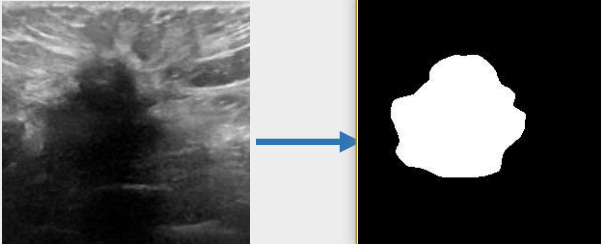

## 算法原理 U-KAN与其它图像分割算法一样,将图片数据送入模型后,依次通过预处理、特征提取,最后经过卷积预测出像素类别实现分割。

## 环境配置 ``` mv U-KAN-optimize_pytorch U-KAN # 去框架名后缀 # if torch>2.0, modify /usr/local/lib/python3.10/site-packages/timm/models/layers/helpers.py: from torch._six import container_abcs -> import collections.abc as container_abcs ``` ### Docker(方法一) ``` docker pull image.sourcefind.cn:5000/dcu/admin/base/pytorch:2.1.0-ubuntu20.04-dtk24.04.1-py3.10 # 为以上拉取的docker的镜像ID替换,本镜像为:a4dd5be0ca23 docker run -it --shm-size=32G -v $PWD/U-KAN:/home/U-KAN -v /opt/hyhal:/opt/hyhal:ro --privileged=true --device=/dev/kfd --device=/dev/dri/ --group-add video --name ukan bash cd /home/U-KAN pip install -r Seg_UKAN/requirements.txt # requirements.txt ``` ### Dockerfile(方法二) ``` cd U-KAN/docker docker build --no-cache -t ukan:latest . docker run --shm-size=32G --name ukan -v /opt/hyhal:/opt/hyhal:ro --privileged=true --device=/dev/kfd --device=/dev/dri/ --group-add video -v $PWD/../../U-KAN:/home/U-KAN -it ukan bash # 若遇到Dockerfile启动的方式安装环境需要长时间等待,可注释掉里面的pip安装,启动容器后再安装python库:pip install -r Seg_UKAN/requirements.txt。 ``` ### Anaconda(方法三) 1、关于本项目DCU显卡所需的特殊深度学习库可从光合开发者社区下载安装: - https://developer.hpccube.com/tool/ ``` DTK驱动:dtk24.04.1 python:python3.10 torch:2.1.0 torchvision:0.16.0 ``` `Tips:以上dtk驱动、python、torch等DCU相关工具版本需要严格一一对应。` 2、其它非特殊库参照requirements.txt安装 ``` pip install -r Seg_UKAN/requirements.txt # requirements.txt ``` ## 数据集 `BUSI(Breast Ultrasound Image)` - https://www.kaggle.com/datasets/aryashah2k/breast-ultrasound-images-dataset 本项目无需下载原始数据集,采用U-KAN作者提供的预处理数据[pre-processed dataset](https://mycuhk-my.sharepoint.com/:f:/g/personal/1155206760_link_cuhk_edu_hk/ErDlT-t0WoBNlKhBlbYfReYB-iviSCmkNRb1GqZ90oYjJA?e=hrPNWD) 即可。 项目中已包含[`busi`](./Seg_UKAN/inputs/busi.zip),解压即可使用,训练数据目录结构如下: ``` Seg_UKAN ├── inputs │ ├── busi │ ├── images │ ├── malignant (1).png | ├── ... | ├── masks │ ├── 0 │ ├── malignant (1)_mask.png | ├── ... ``` ## 训练 ### 单机单卡 ``` # 以公开数据集busi为基础进行算法效果优化 cd Seg_UKAN python train.py --arch UKAN --dataset busi --input_w 256 --input_h 256 --name busi_UKAN --data_dir ./inputs ``` 更多资料可参考源项目的[`README_origin`](./README_origin.md) ## result

### 精度 数据集:busi,max epoch为400,训练框架:pytorch。 | 算法 | Dice | |:---------:|:------:| | U-KAN | 78.75% | | U-KAN-optimize | 79.64% | ## 应用场景 ### 算法类别 `图像分割` ### 热点应用行业 `医疗,电商,制造,能源` ## 源码仓库及问题反馈 - http://developer.hpccube.com/codes/modelzoo/u-kan-optimize_pytorch.git ## 参考资料 - https://github.com/CUHK-AIM-Group/U-KAN.git - https://github.com/KindXiaoming/pykan.git - https://kindxiaoming.github.io/pykan/